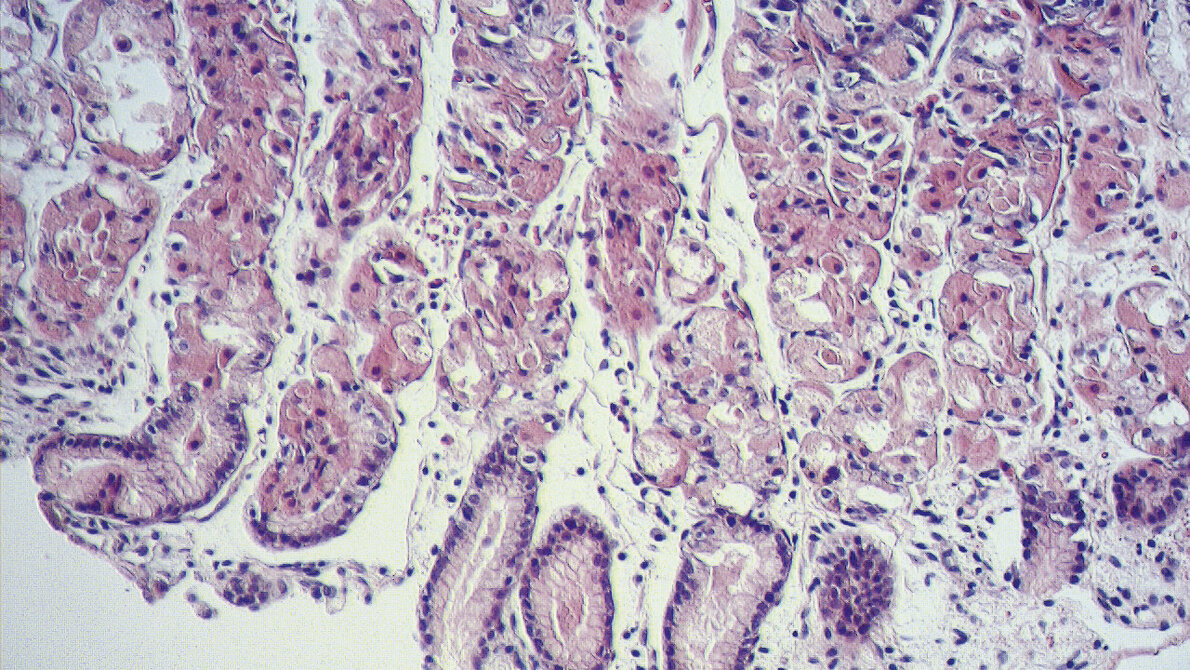

Der Magen ist ein Transport- und wichtiges Verdauungsorgan. Krankheiten können durch ein Missverhältnis zwischen aggres-siven und schützenden Faktoren im Magen entstehen. Dies geschieht, wenn die mechanische und sekretorische Leistung gestört ist. Die häufigste Erkrankung des Magens ist die Gastritis, die zwischen 60–70 % durch eine Besiedelung von Helicobacter pylori ausgelöst wird. Bei chronischen Gastritiden kann es zu so starken Zellveränderungen kommen, dass daraus maligne Erkrankungen des Magens entstehen können. Um diese Erkrankungen differenzialdiagnostisch unterscheiden zu können, kommt die Immunhistochemie zum Einsatz.